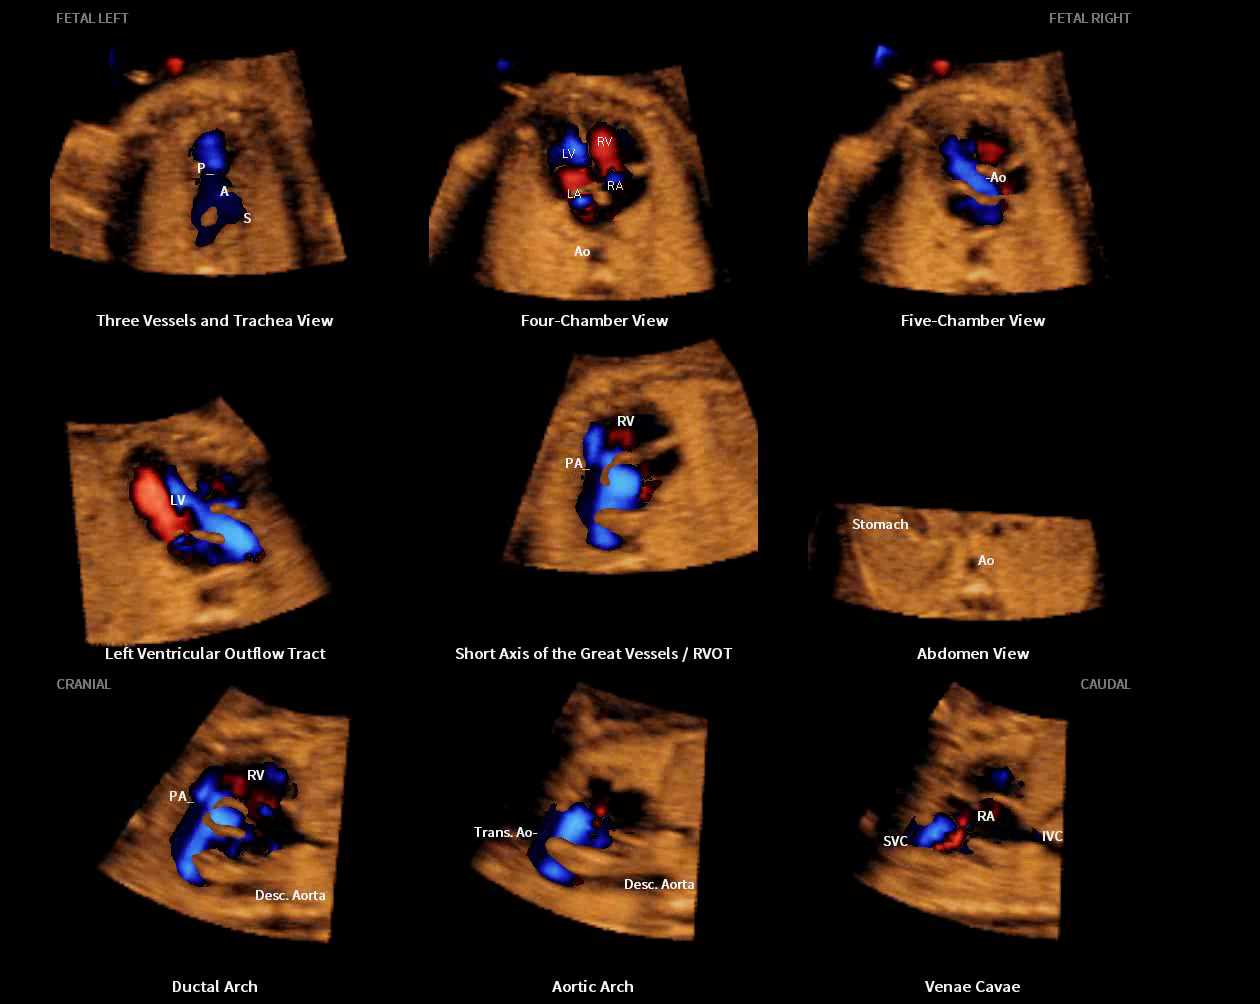

Professor Lami Yeo, M.D., from the Department of Obstetrics and Gynecology at the Wayne State University School of Medicine in Detroit, U.S., presented research on the diagnostic performance of Fetal Intelligent Navigation Echocardiography (5D Heart™) which showed a sensitivity of 98%, specificity of 93%, and accuracy of 95% for the prenatal detection of congenital heart disease*. She also explained that 5D Heart™ offers a rapid and simple solution to screen for and diagnose congenital heart disease by generating nine standard fetal echocardiography views in a single template display.

Additionally, novel research conducted on color Doppler Fetal Intelligent Navigation Echocardiography (5D Heart Color™) will be published in the October 2017 issue of the scientific journal Ultrasound in Obstetrics & Gynecology (UOG), which will also feature on its front cover, the prenatal diagnosis of congenital heart disease using 5D Heart color™.